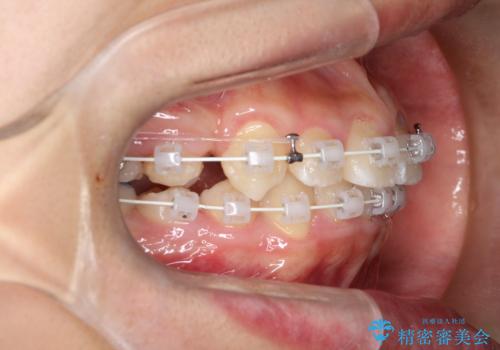

八重歯・歯並びのデコボコとディープバイトを改善した抜歯ワイヤー矯正症例

- ワイヤー(審美装置)

矯正の精密検査の結果上顎左右4番の計2本を抜歯し、審美性に配慮したワイヤー矯正装置(審美装置)を用いて治療を行いました。

八重歯などの歯列のデコボコが綺麗に改善され、患者様にも大変喜んでいただけました。また、咬み合わせが深い「ディープバイト」も併せて改善し、見た目だけでなく機能面でもバランスの取れた咬合を獲得しています。